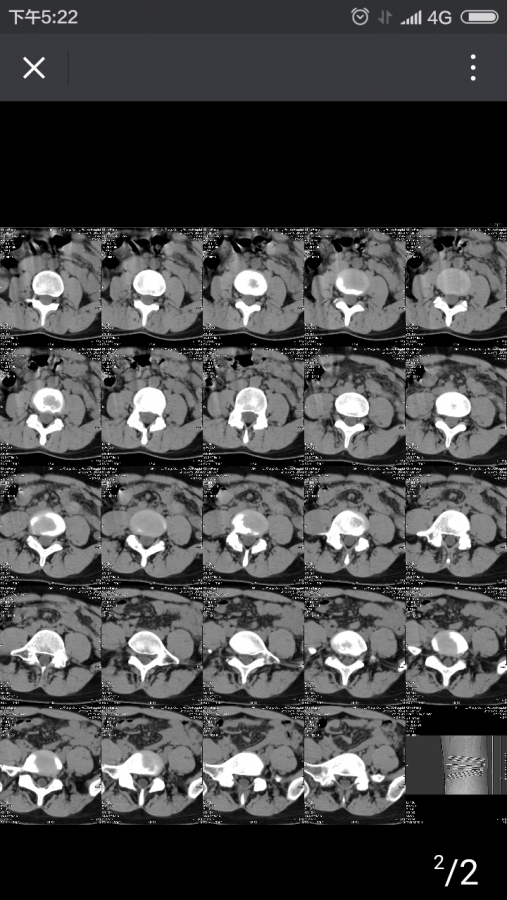

不小心把腰给扭了,扭的是左腰,去医院拍了CT,CT图如下,扭伤两天后,左腰基本无痛感,但是现在右侧隐隐作痛,请问这是怎么回事? 以前从未腰痛过……今年七月检查有肾结石,是否是肾结石引起的腰痛? Screenshot_2016-11-24-17-22-07_com.tencent.mm.png |